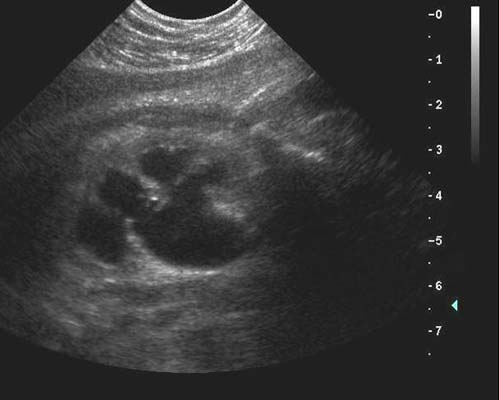

Anéchogène ovalaire